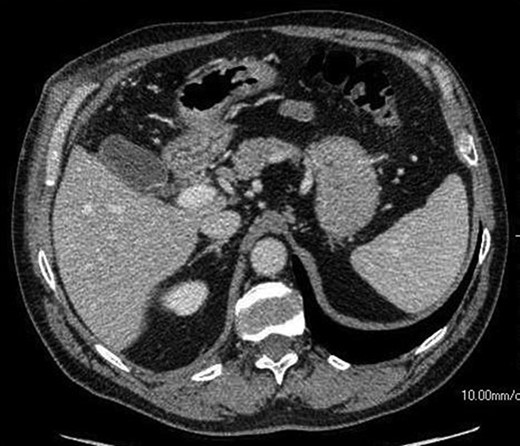

The patient presented to the hospital 4 months after the initial operation with right upper quadrant pain. CT abdomen established the appearance of a normal gallbladder despite his history of subtotal cholecystectomy (Fig. 2). He underwent an elective laparoscopic cholecystectomy 1 month later, which revealed an apparently complete gallbladder that was extensively walled off by omentum. An intraoperative image is shown in Fig. 3.

An axial CT image shows collection in the gall bladder fossa closely resembling a normal gallbladder appearance.